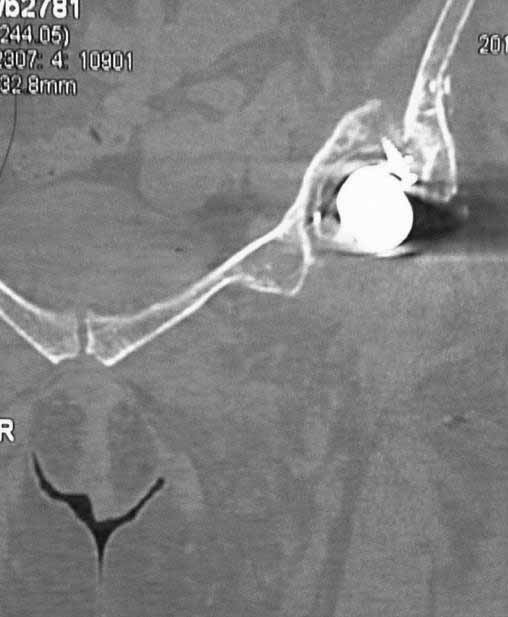

Уважаемые коллеги. Хотелось бы услышать мнения и советы по представляемому случаю. Пациентка 45 лет. Бесцементное эндопротезирование левого тазобедренного сустава 6 лет назад (впадина RM, Mathys, металл-металл, ножка Зульцеровская). За 10 лет до протезирования – коррегирующая остеотомия бедренной кости, которая не срослась в течение года до удаления пластины, а затем срослась в течение 3 месяцев иммобилизации в кокситной повязке. После протезирования получилось наблюдать пациентку почти постоянно, поскольку через 2 года синтезировал ей лодыжки на оперированной стороне, затем, через несколько месяцев удалил фиксаторы, а в 2009г. резецировал мениск на противоположной стороне. Боли все эти годы не беспокоили. Пациентка чуть выше среднего роста, вес тела нормальный. Физические нагрузки переносила хорошо. Работает на 7 этаже без лифта. Год назад экстирпация матки по поводу лейомиомы больших размеров. Несколько месяцев назад появились боли в области левого тазобедренного сустава. При рентгеновском и КТ исследованиях (июль с.г.) – нестабильность тазового компонента. От предложенной замены протеза пациентка на тот момент, слава богу, отказалась. Через какое то время боли в области левого тазобедренного сустава практически полностью прошли, а около 2 месяцев назад появилось ощущение патологической подвижности таза и боли в паху справа, которые через некоторое время уменьшились, а потом снова усилились после значительных физических нагрузок (много ходила по песку на пляже, носила тяжести). Ежедневно принимала диклофенак. На рентгенограммах – переломы правой лонной кости. Сейчас госпитализирована из-за болей в паху справа. Боли слева не беспокоят. На фоне снижения нагрузок в стационаре боли значимо уменьшились. Способна ходить без средств дополнительной опоры.В анализах крови чуть повышены трансаминазы и гамма-ГТ, моча без особенностей.

Вопросы: -правильно ли я расцениваю переломы как стрессовые на фоне неполноценного таза (pelvic insufficiency stress fractures)? -Можно ли так же расценить ситуацию на стороне протеза и, соответственно, не торопиться с ревизией, рассчитывая на вторичную стабилизацию? Уж больно не хочется менять ножку. -Если думать о ревизии, то когда? На представленных снимках тазобедренный сустав до и сразу после операции, затем 2 снимка 2009г., когда ничего не беспокоило, затем КТ 2-х месячной давности и вчерашние рентгенограммы обоих тазобедренных суставов.

Сергей, очень возможно, что перелом и стрессовый, но мне видится, что его причина в нестабильности чашки. Дело в том, что в отличии от ножек, чашка при своей дестабилизации болит гораздо меньше и больные терпят до последнего.

При сравнении рентгенограмм можно увидеть насколько чашка переместилась от места своего первичного расположения. От опрокидывания ее удерживают конструкционные элементы "рожки". Без них ситуация, возможно, уже была бы катастрофической (чашка в тазу). Думаю надежды на вторичную интеграцию, могут быть обмануты и ревизии не избежать.

Если внимательно посмотреть на рентгеновские снимки, то видно, что пара трения действительно металл-металл.